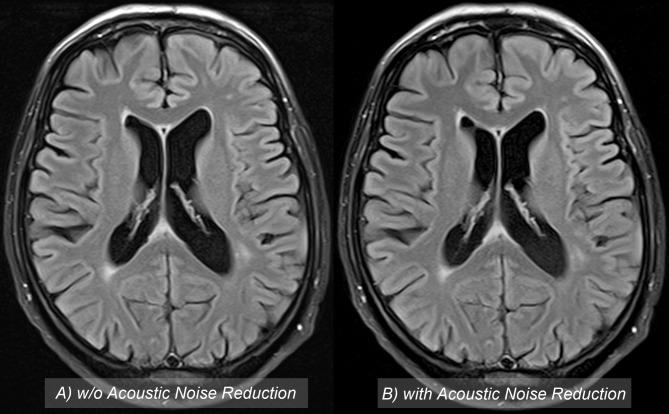

To investigate acoustic noise reduction, image quality and white matter lesion detection rates of cranial magnetic resonance imaging (MRI) scans acquired with and without sequence-based acoustic noise reduction software.

Peak sound pressure levels were slightly but significantly reduced using QS, P≤0.017. Effective sound pressure, measured in Pascal, was decreased by 19.7%. There was no significant difference in subjective image quality between FLAIR sequences acquired without/with QS: observer 1: 2.03/2.07, P = 0.730; observer 2: 1.98/2.10, P = 0.362. In addition, SNR was significantly increased in white matter, P≤0.001, and gray matter, P = 0.006, using QS. The lesion detection rates did not decline utilizing QS: observer 1: P = 0.944 observer 2: P = 0.952.

Sequence-based noise reduction software such as QS can significantly reduce peak sound pressure levels, without a loss of subjective image quality and increase SNR at constant lesion detection rates.